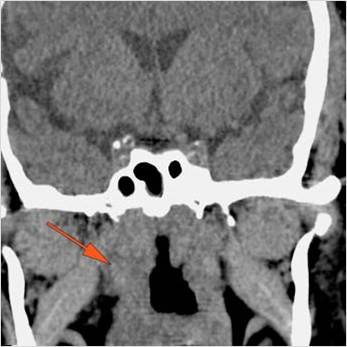

74-year old insulin-dependent diabetic female in the emergency room with fever, sinusitis with possible orbital, intracranial or other complications such as cavernous sinus thrombosis.Exam

Findings are consistent with the clinical diagnosis of acute or subacute ethmoid and most importantly sphenoid sinusitis, possibly fungal, with left superior ophthalmic vein thrombosis, early tension orbit and cavernous sinus thrombosis.